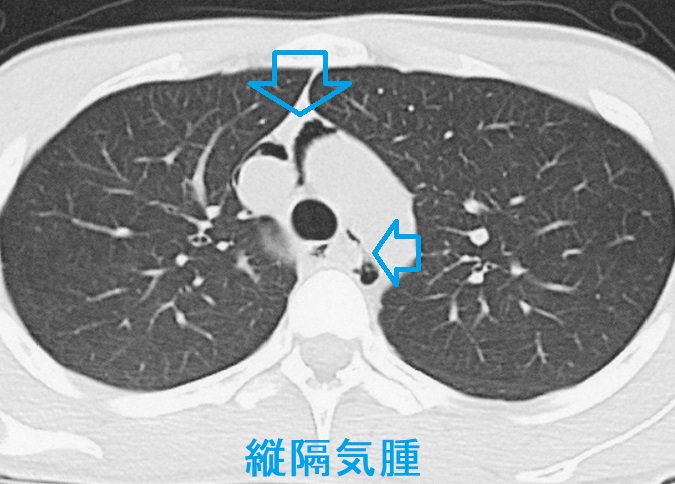

心臓震盪(しんぞうしんとう)でなく縦隔気腫

サッカーボールが胸を直撃した場合、肺胞が破裂し、肺間質へ侵入した空気が縦隔へ移動→縦隔気腫→皮下気腫がおきる場合もあります。

頸部の違和感が主訴になるため、甲状腺の病気と勘違いすることもあります。肉眼上、頸部皮膚に異常がないものの、独特の握雪感を認めるため、皮下気腫の存在がわかります。呼吸音に異常を認めません。胸部単純CTで縦隔気腫の診断を確定。

縦隔気腫の治療は、

- 入院安静で自然軽快する場合が多い

- 血胸、気胸があれば胸腔ドレナージ

- 緊張性縦隔気腫で心臓・血管・肺を圧迫すれば縦隔ドレナージ